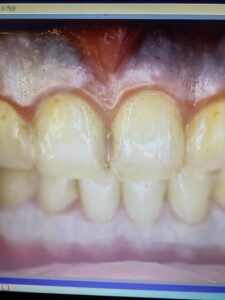

初診時の写真(複製で吸すいません)

上下ともメラニン沈着がみられますね。